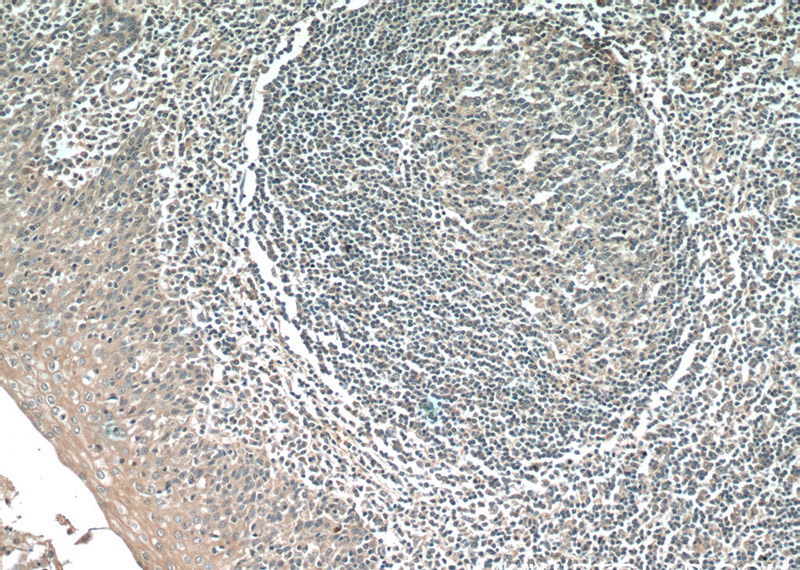

Immunohistochemistry of paraffin-embedded human tonsillitis tissue slide using Catalog No:107333(NINJ2 Antibody) at dilution of 1:50 (under 10x lens)